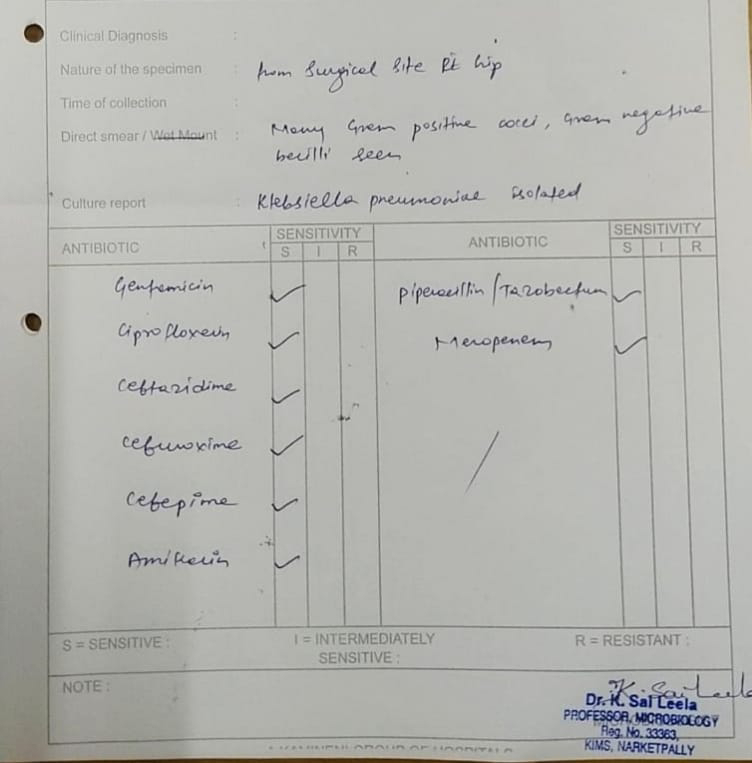

[8/8, 7:40 PM] PaJR PHR Moderator: Growing organisms in the bed sore doesn't prove that they have any role in the delayed healing of the bed sore. It's just that these organisms are also in his bed

[8/8, 7:42 PM] PaJR PHR Moderator: Inspite of the E coli grown in his urine, he hasn't had any symptoms due to this UTI except for one episode of pus showing in the catheter.